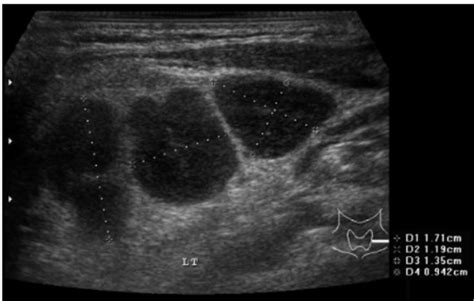

b超图有圆形有茄子形这是啥意思

孕囊的数据看不懂,大家来帮我看看是长型还是圆形的。

的确挺圆的,都说那三个数据是,长*宽*厚,说长圆,都是按前面两数字比较的,[:em30:] 我觉得这个不准,大家娱乐罢了[:em30:]

我想不一定的吧,我看有的jm说孕囊形状会变的,而且不同医生查看的角度不一样,孕囊也会有点出入的。我今天b超看了孕囊32*32那一定是女宝咯?呵呵我喜欢女宝